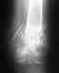

Диагноз: Посттравматическая комбинированная контрактура 2 пальца правой кисти. Уменя после операции стала видна кость на кончике 2 пальца правой кисти мой лечащий врач Тягунов Денис Евгеньевич 13 ортопедическое отделение подскажите , что мне делать в данной ситуации